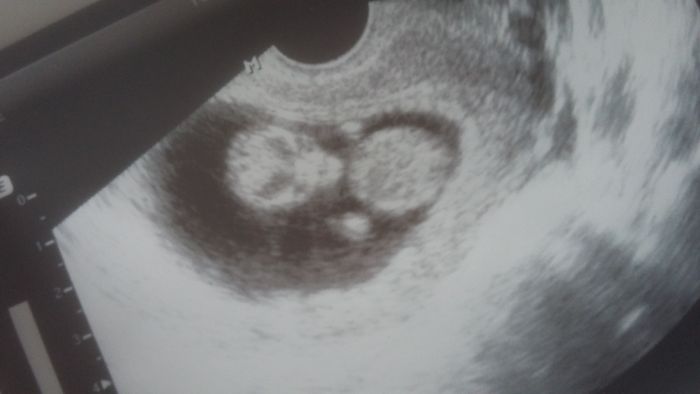

Ja jsem vcera taky byla na prvnim screeningu, podle ultrazvuku vse v poradku, srdicko bilo jako zvon, ukazal i mocovy mechyr a zaludek, pocital prsticky

Pridavam i fotku naseho ufonka